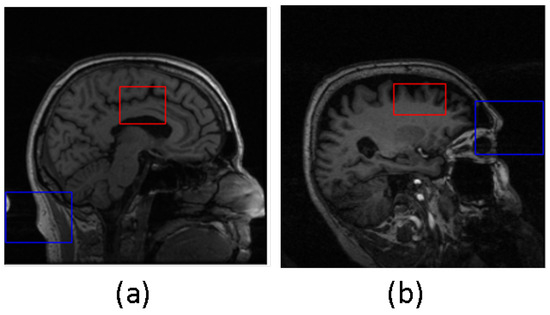

In our RL-based approach, we have defined a set of five actions: Up, Down, Left, Right, and Terminate (refer to Figure 4). The action Up shifts the bounding box in the image vertically by 5 positions, while Down moves it downward by 5 units along the y-axis. Similarly, Left and Right actions result in the bounding box moving horizontally by 5 units to the left and right along the x-axis, respectively. The Terminate action ends the episode and the DQN model generates the bounding box that encompasses the desired region of interest. For our 3D-based localization, we have introduced two additional actions: Top and Bottom. When Top is selected, the bounding box moves upward along the depth (z-axis) of the sample by 5 units. Conversely, the Bottom action causes the bounding box to descend in depth along the z-axis by 5 units.

Figure 4.

Experimental setup with agent shown as the red box and arrows depicting the permissible actions for (a) 2D data and (b) 3D data. In the case of 2D data, there are five actions available (Up, Down, Left, Right, and Terminate), while for 3D data, there are two additional actions, including Top and Bottom.